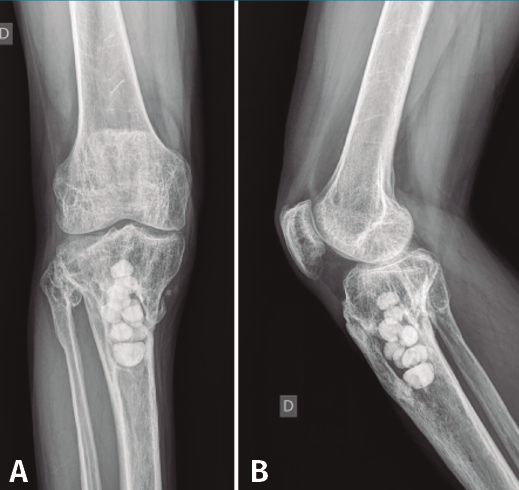

En el estudio radiológico (Figura 5) se objetiva imagen cavitaria en el extremo proximal de la tibia con presencia de material granulado del injerto realizado.

Con el diagnóstico de osteítis crónica de la tibia se realiza desbridamiento óseo de la cavidad y amplia resección ósea de cortical tibial medial, y relleno de la cavidad con bolas de cemento con antibiótico (Figura 7), con posterior tratamiento antibiótico.

Figura 5. Radiografías de frente y de perfil del extremo proximal de la tibia donde se objetiva la cavidad en la tibia con presencia de material granulado en su interior.

Figura 7. Radiografías de frente y de perfil del extremo proximal de la tibia tras el desbridamiento de la cavidad y el relleno con bolas de cemento con antibiótico.